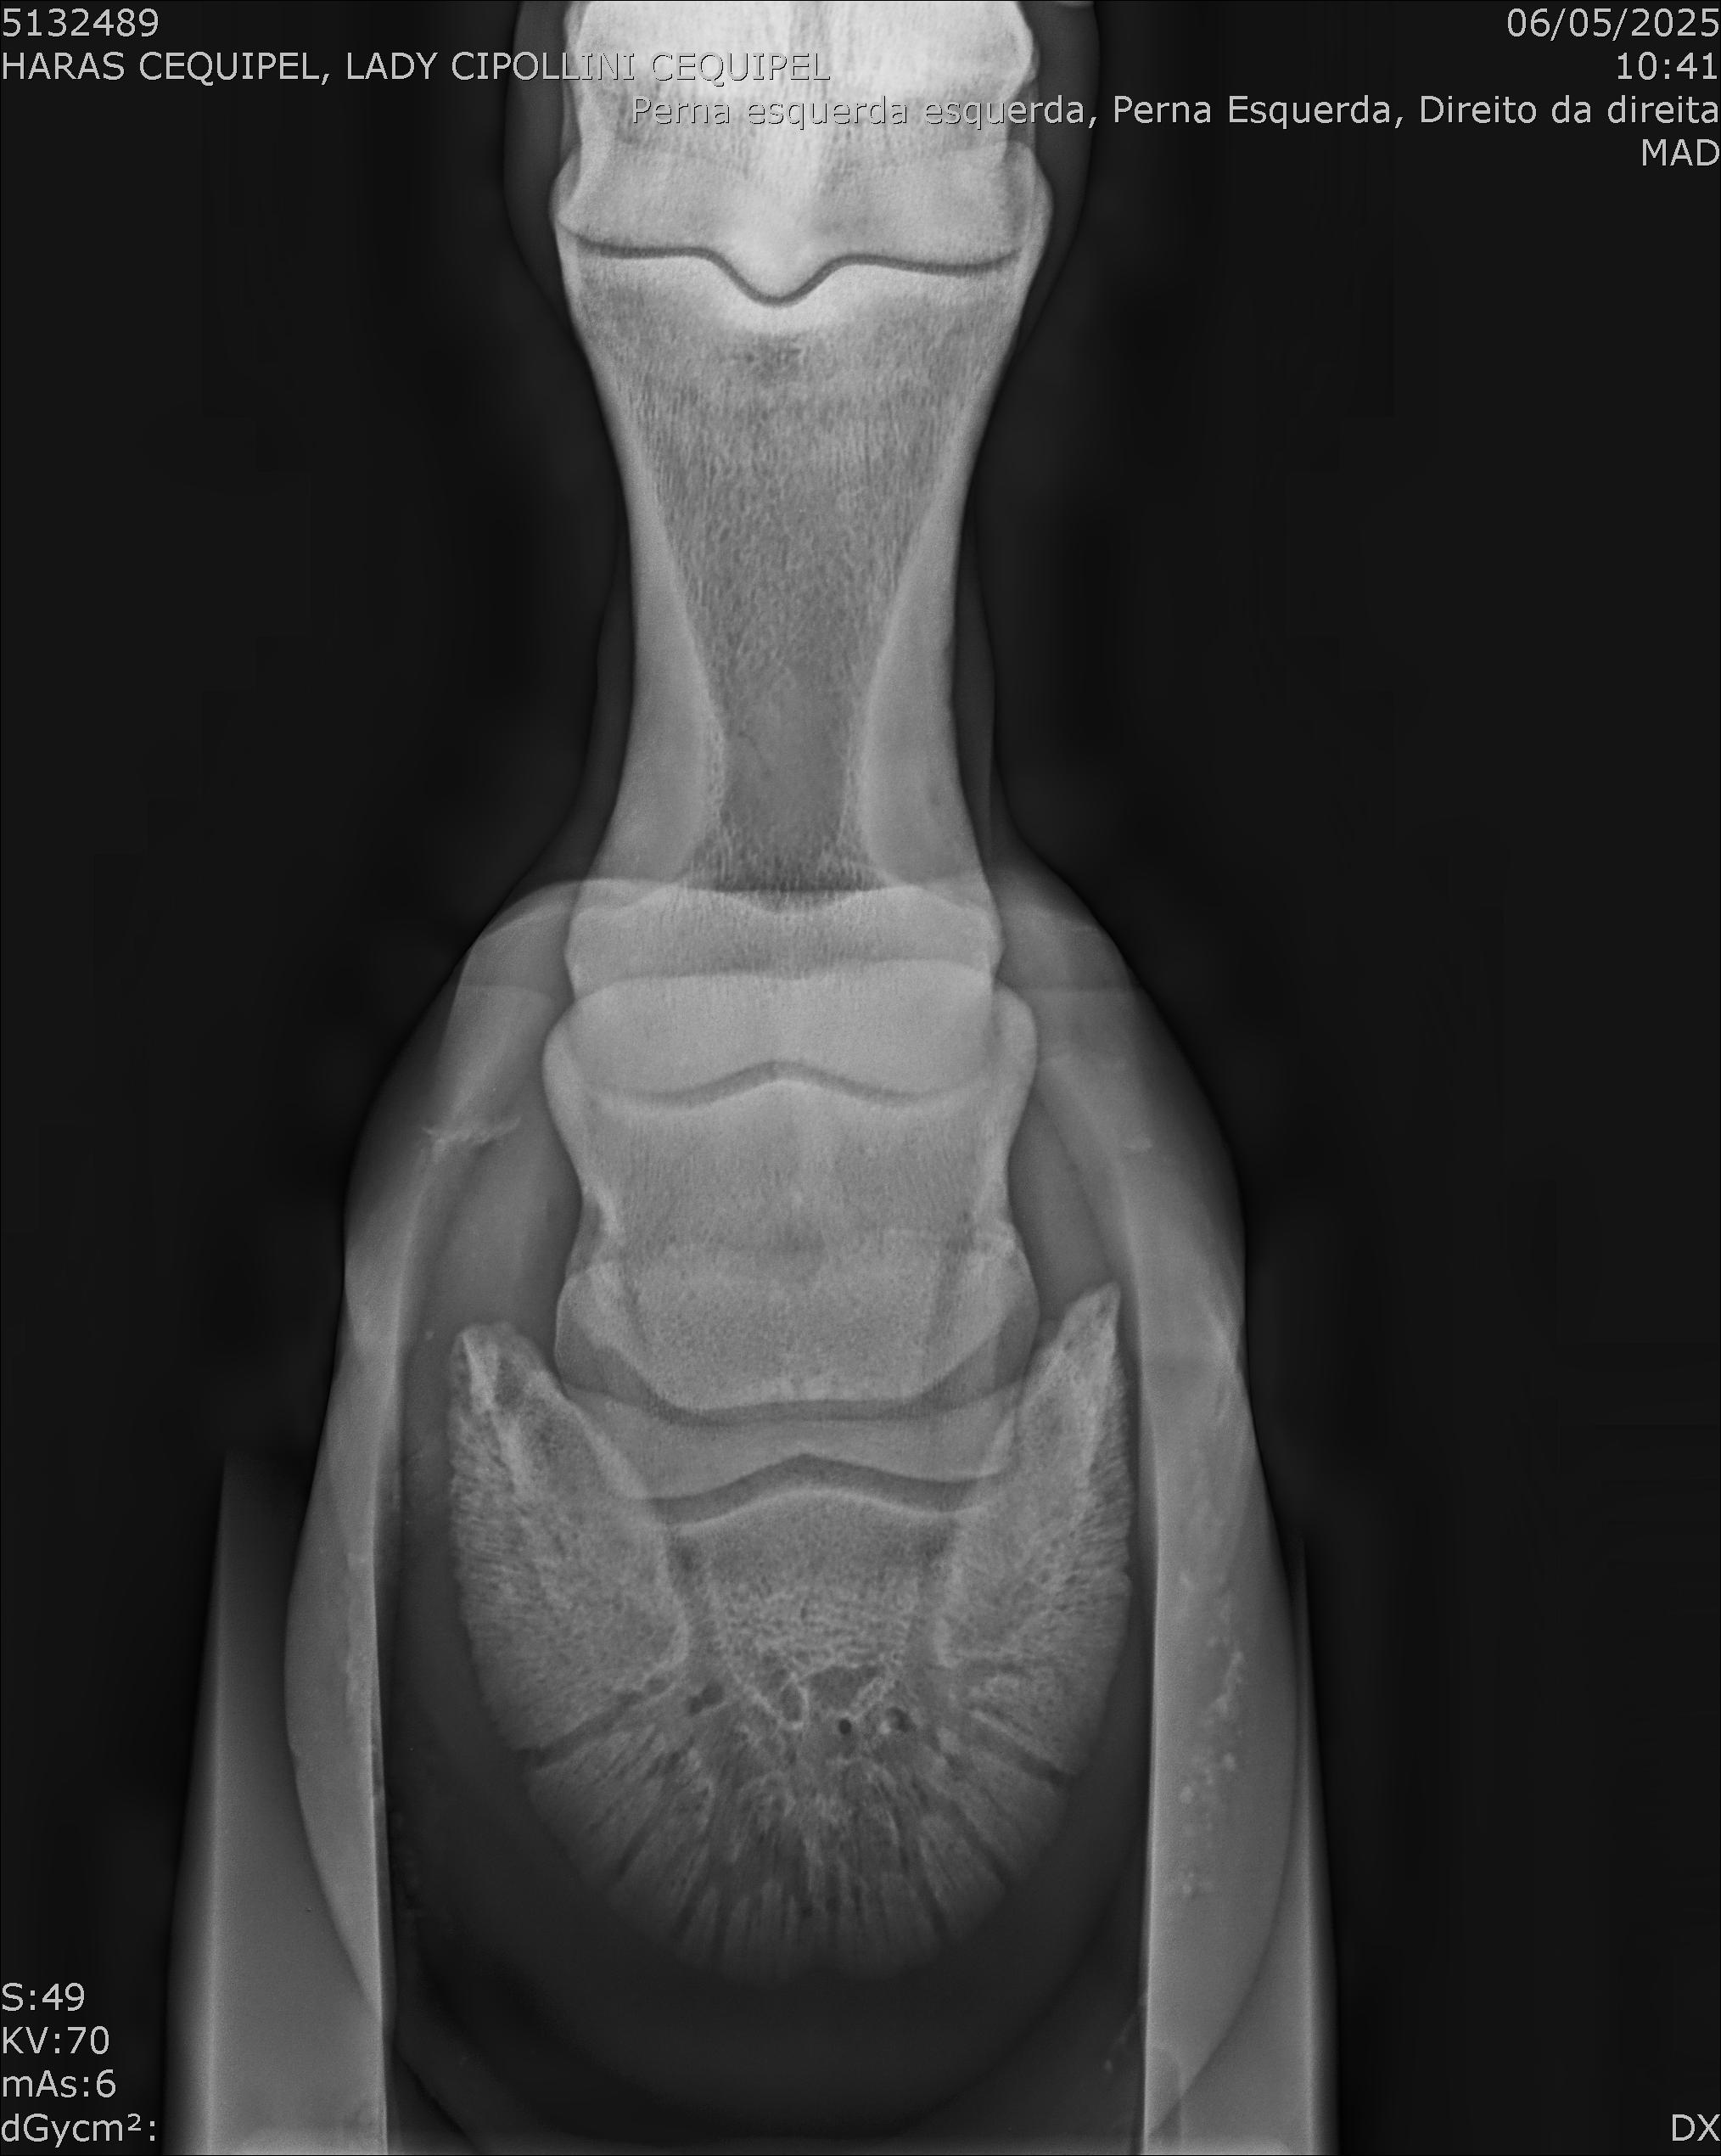

:: RAIOS-X DO LOTE